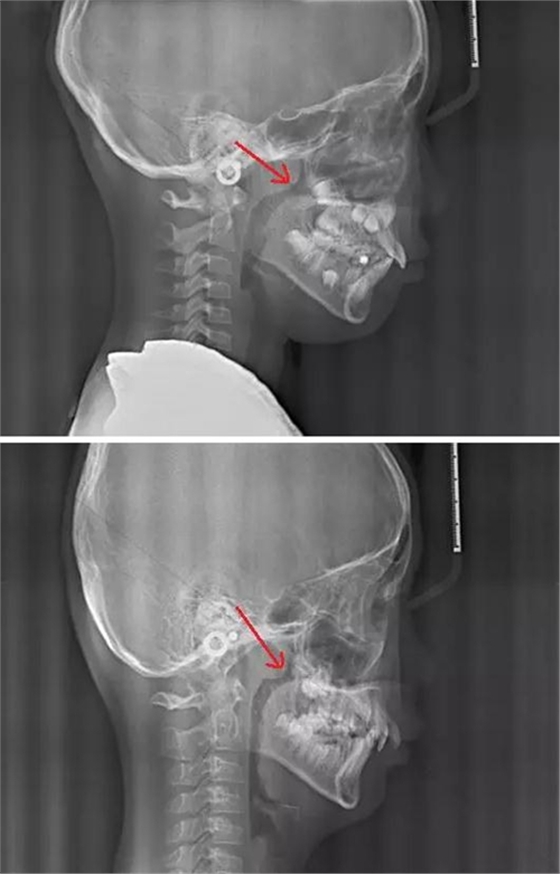

賀老師提到兒童青少年最常見的兩種阻塞呼吸道的問題即腺樣體肥大和扁桃體肥大。首先我們通過頭顱側(cè)位片來了解一下這兩個腺體在x線片上的位置。

以下兩張標(biāo)注的是肥大的腺樣體及其位置

我們再來看兩張肥大的扁桃體